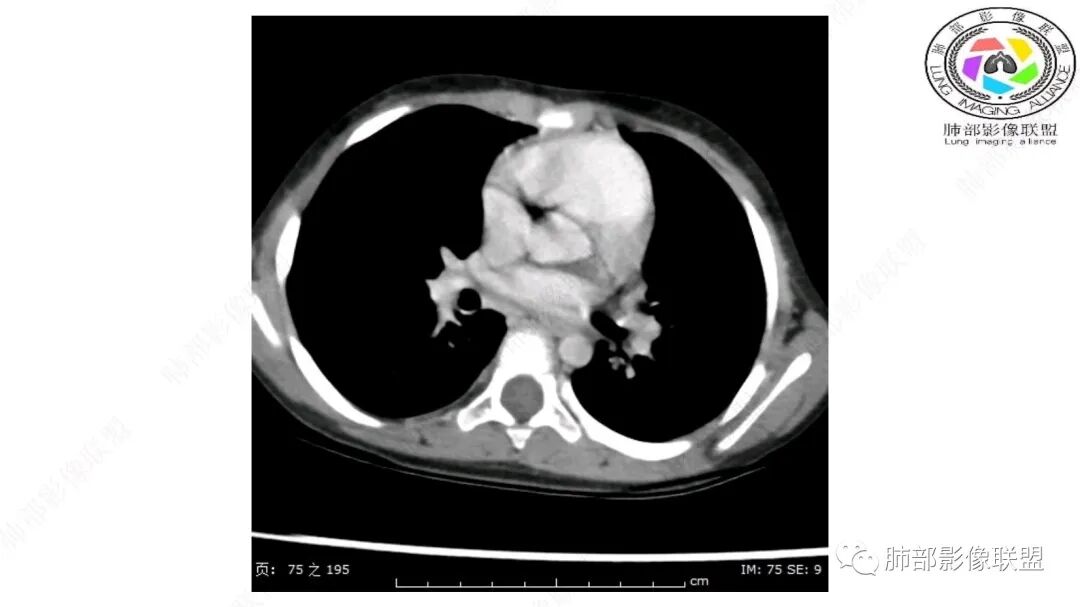

第一个问题:定位:肺内?纵隔?

病灶属于交界区,主体位于肺内,占位效应明显,前方突入胸壁,胸腺受压变形,胸膜显示欠清楚;病灶包绕上叶肺动脉;似乎有体动脉供血。符合肺内的点:包绕上叶肺动脉分支;符合纵隔的点:前方似乎突入胸壁,与胸腺关系比较密切,但是与上腔静脉的关系提示病灶不支持纵隔来源,前纵隔的常规会将上腔静脉受压后移、外移,这是不符合的。

从这个角度符合肺内的,有一点不太踏实的是:似乎突入前胸壁。

2.肺动脉穿行也许是肺内来源最重要支持点!